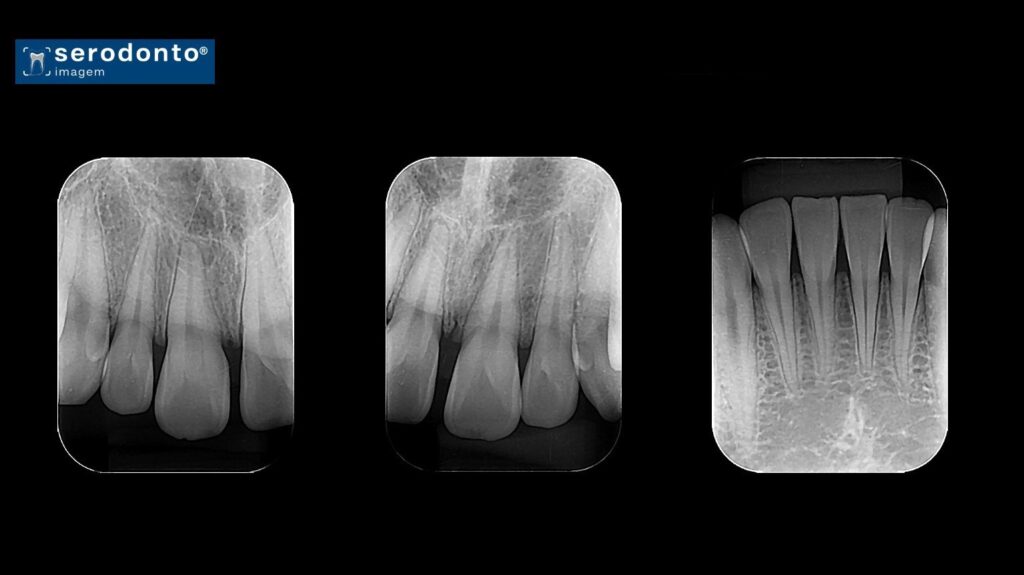

A radiografia periapical oferece uma visão detalhada da coroa, raiz e estruturas adjacentes de um ou mais dentes.

Identificação de lesões periapicais.

Avaliação de cáries e fraturas dentárias.

Planejamento de tratamentos endodônticos.

Monitoramento de condições periodontais.